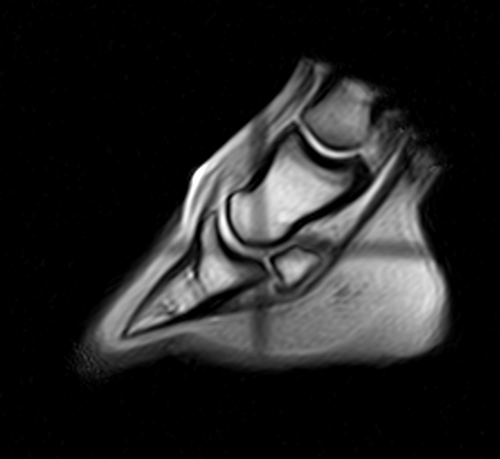

Seit 2004 arbeiten wir mit der Magnet-Resonanz-Tomographie (MRT) als Diagnosemethode. Es handelt sich um ist ein bildgebendes Verfahren zur Darstellung der verschiedenen Gewebe mit Hilfe eines starken Magnetfeldes. Ohne den Einsatz von Röntgenstrahlen werden Schichtaufnahmen des betroffenen Areals angefertigt.

Durch die MRT Technik ist es uns möglich Aussagen über den Zustand von Weichteilgewebe wie Bänder, Sehnen, Gelenkkapsel, Knorpel oder Schleimbeutel zutreffen. Dadurch ist insbesondere der Bereich der Hufrolle, der sich im für den Tierarzt nur bedingt zugänglichen Hornschuh befindet, mittels MRT genauestens zu untersuchen. In unserer Klinik verwenden wir ein Gerät, das die Untersuchung am stehenden, lediglich sedierten Pferd ermöglicht. Eine risikoreiche Narkose ist somit nicht mehr nötig. Der U-förmige Magnet ist höhenverstellbar, sodass Regionen vom Hufbereich bis zum Vorderfußwurzel- bzw. Sprunggelenk untersucht werden können.

MRT des Fesselgelenkes

MRT des Hufes